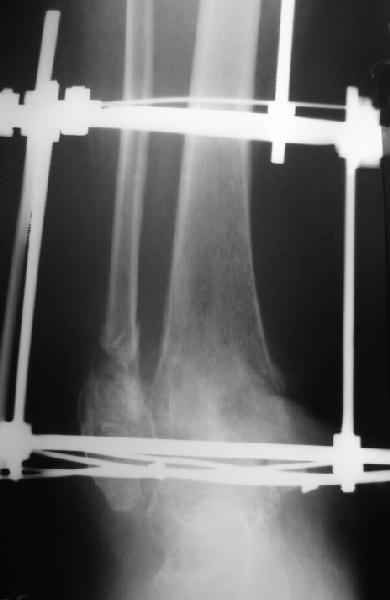

Пациентка 56лет поступила через 5,5 мес. после открытого 2-х лодыжечного перелома, наружного вывиха правой стопы, осложнённого гнойным артритом.

через 3 недели после травмы в ОКБ выполнена артротомия, некрсеквестрэктомия б/берцовой кости, ещё через неделю - аутодермопластика по Тиршу. К нам больная поступила через 5,5 мес. Выполнен ЧКО, остеотомия м/берцовой кости, аппаратное вправление вывиха. Планируется артродез голеностопного сустава. По медиальной поверхности голени на месте аутодермопластики сформировался грубый рубец, спаянный с б/берцовой костью. Больная ходит на костылях с частичной опорой на правую стопу. ВОПРОС: 1) возможно ли в данной ситуации обойтись компрессионным артродезом в АВФ?2) какой вид кожной пластики и в какие сроки целесообразен?

Возможно, но тогда дополнить аппарат модулями на стопе. На фото стопа в эквинусе. Сомнительно, что фиксация только за таран удержит всю стопу, тем более при разрешенной нагрузке.

"На фото стопа в эквинусе."

Обратите внимание на установку тарана на рентгене!

В самом деле, снимки некачественные - таран в ротации. Но даже по ним видно, что установка стопы минимум 104 градуса. С одной стороны - В Илизаровской технике пишут, что для женщин допустимо и 110. С другой - почему-то в цивилизованном мире настаивают на четких 90.

А если еще лучше присмотреться, таран в переднем подвывихе, что не кажется допустимым.